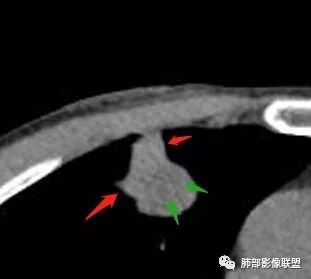

南边:宽基底与胸膜相连桃尖征、U型凹陷、刀切征密度均匀,按理这一部分就是典型的炎性病变的特点

这一部分如何分析?

南边:周围晕、细微毛刺都属于炎性特点这一部分单独拿出来类圆形,边缘光滑,按理恶性特征不明显;但是加在一起,转移瘤就不排除总体倾向于炎性,转移瘤不除外